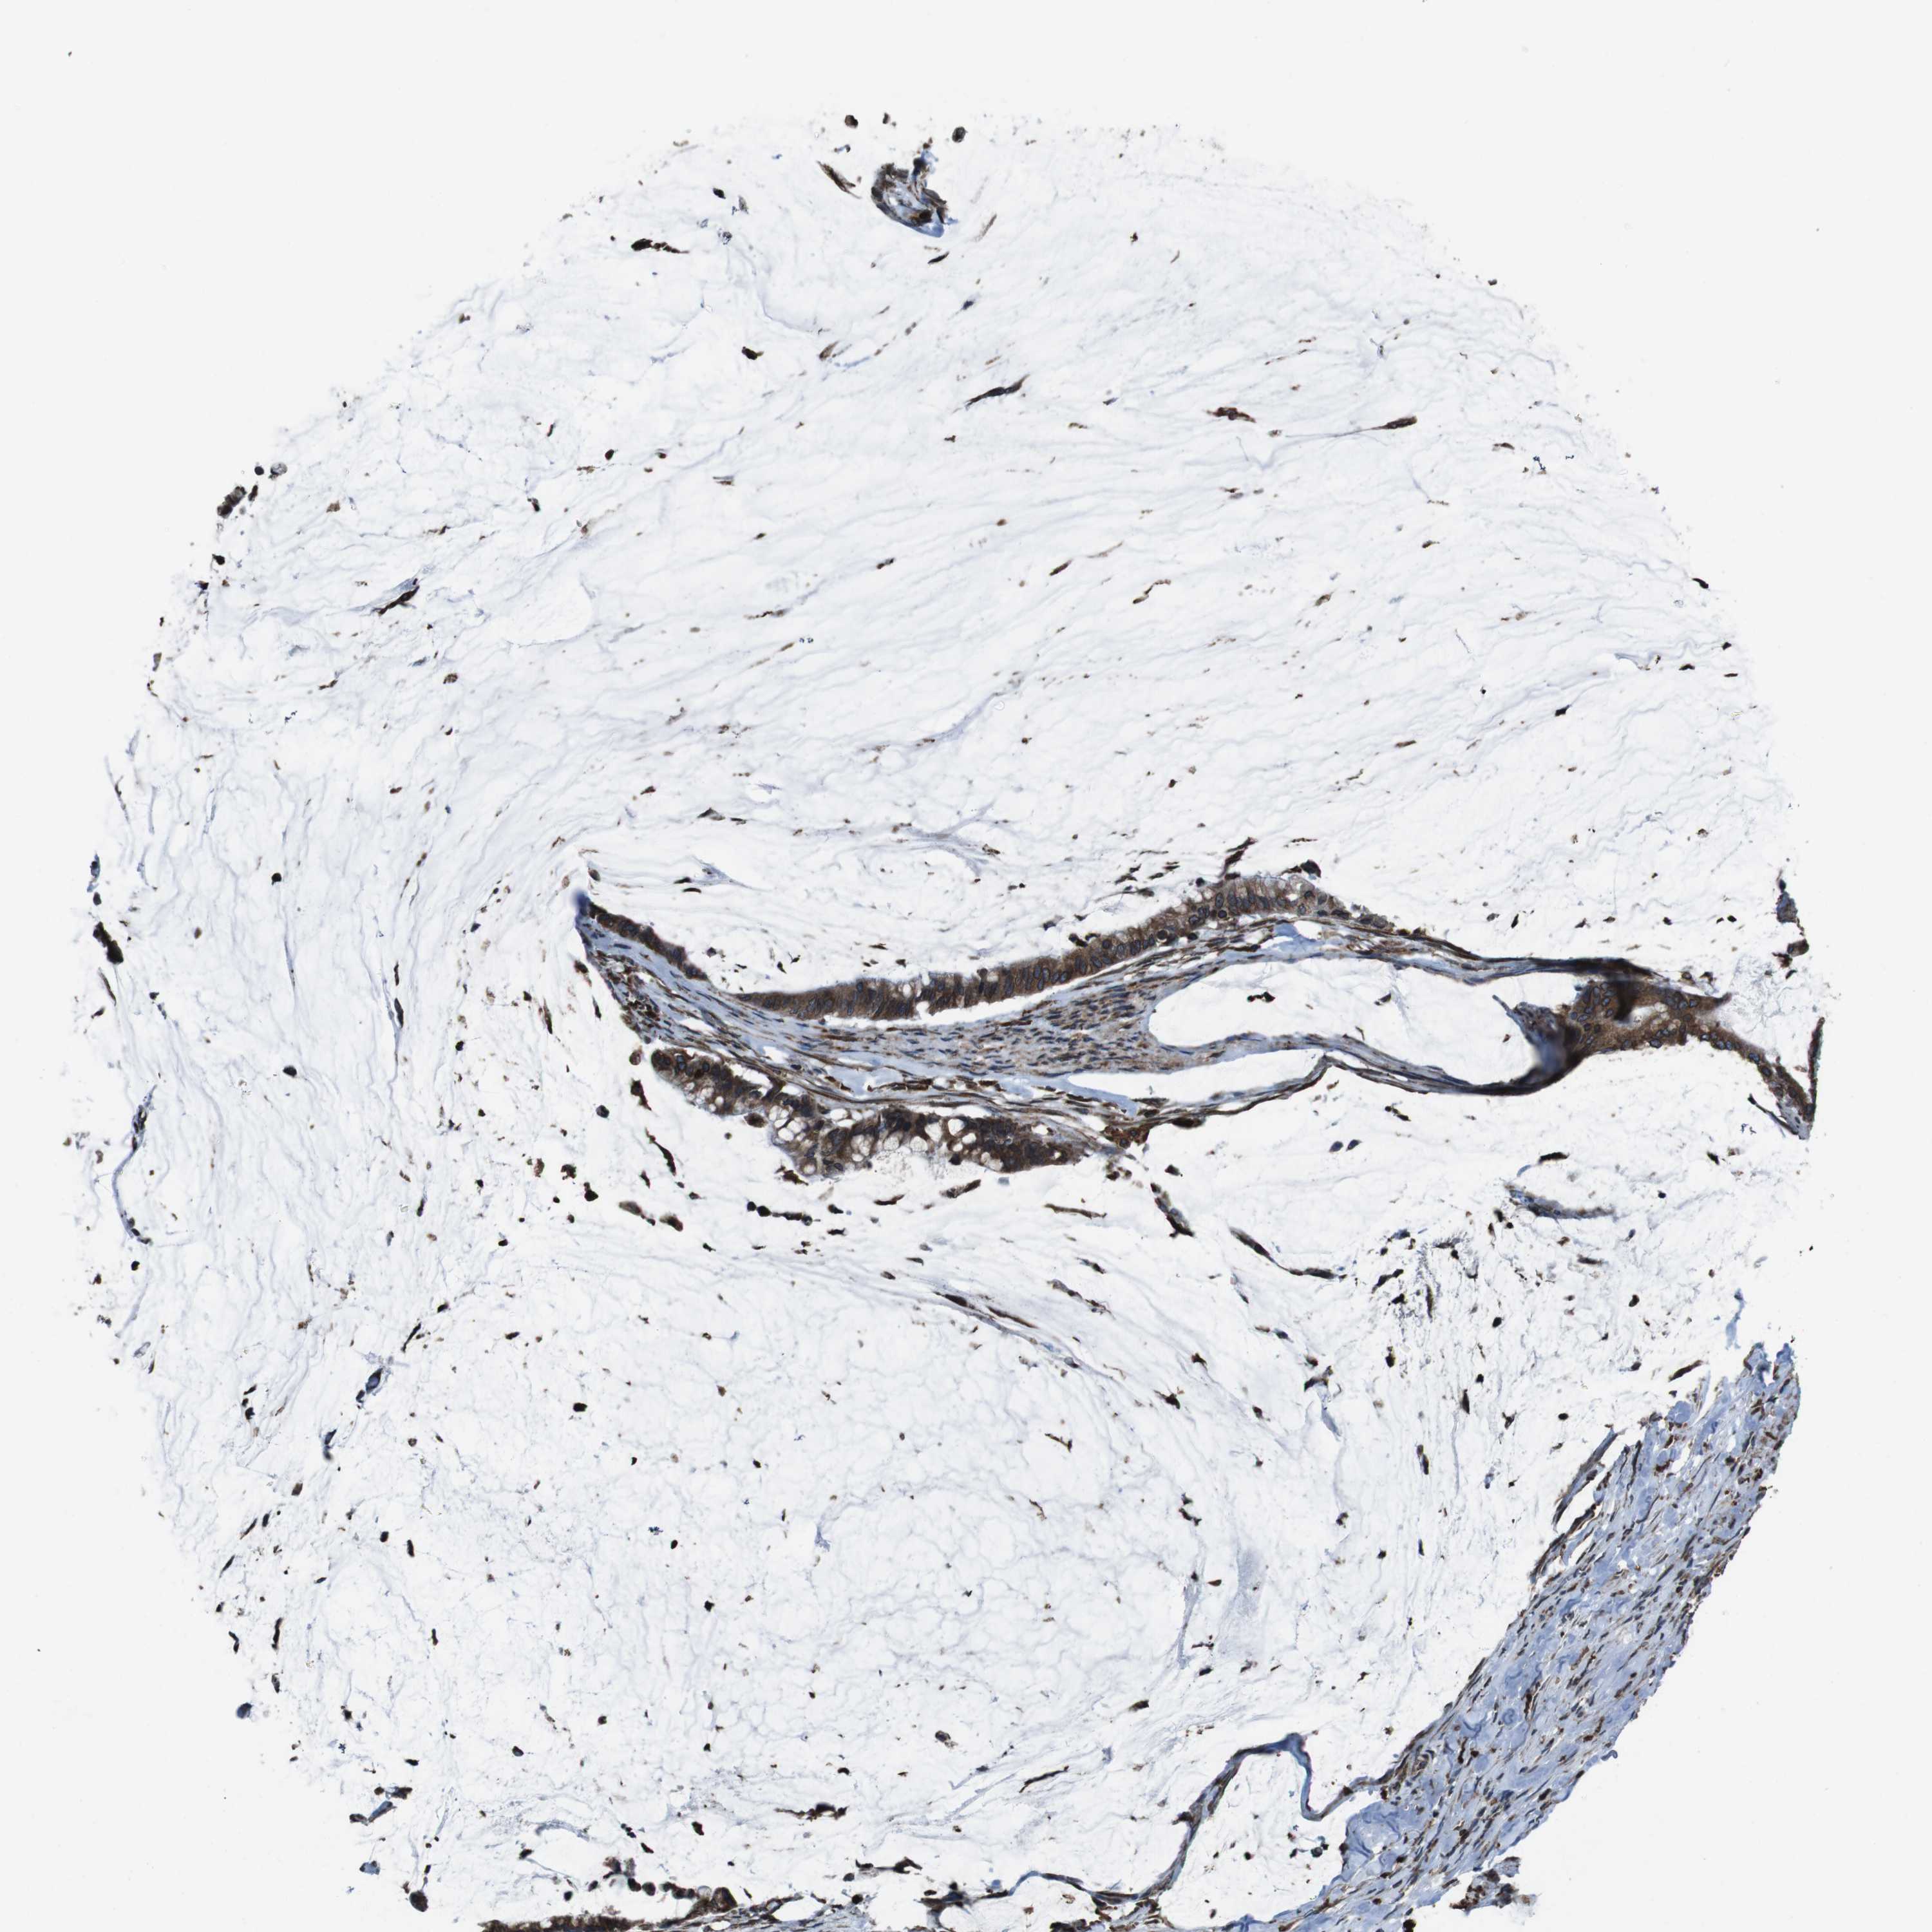

PANCREATIC CANCER - Protein expressioni

A mouse-over function shows sample information and annotation data. Click on an image to view it in a full screen mode. Samples can be filtered based on level of antibody staining by selecting one or several of the following categories: high, medium, low and not detected. The assay and annotation is described here.

Note that samples used for immunohistochemistry by the Human Protein Atlas do not correspond to samples in the TCGA dataset.

Antibody stainingi

Antibody staining in the annotated cell types in the current human tissue is reported as not detected, low, medium, or high, based on conventional immunohistochemistry profiling in selected tissues. This score is based on the combination of the staining intensity and fraction of stained cells.

Each image is clickable and will lead to virtual microscopy that enables deeper exploration of all samples and also displays staining intensity scores, fraction scores and subcellular localization as well as patient and tissue information for each sample.

Antibody HPA012863

Staining

High

Medium

Low

Not detected

Intensity

Strong

Moderate

Weak

Negative

Quantity

>75%

75%-25%

<25%

None

Location

Nuclear

Cytoplasmic/membranous

Cytoplasmic/membranous,nuclear

Adenocarcinoma, NOS